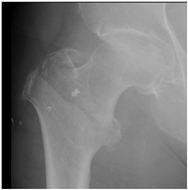

For X-ray 1, four scenarios were developed.![]() | Scenario 1: What would be your operation preference for a mobile patient aged 50–70 and with an ASA score of 1–2? Scenario 2: What would be your operation preference for a mobile patient aged 71 years or older with an ASA score of 1–2? Scenario 3: What would be your operation preference for a mobile patient aged 50–70 with an ASA score of 3–4? Scenario 4: What would be your operation preference for a mobile patient aged 71 years or older with an ASA score of 3–4? |